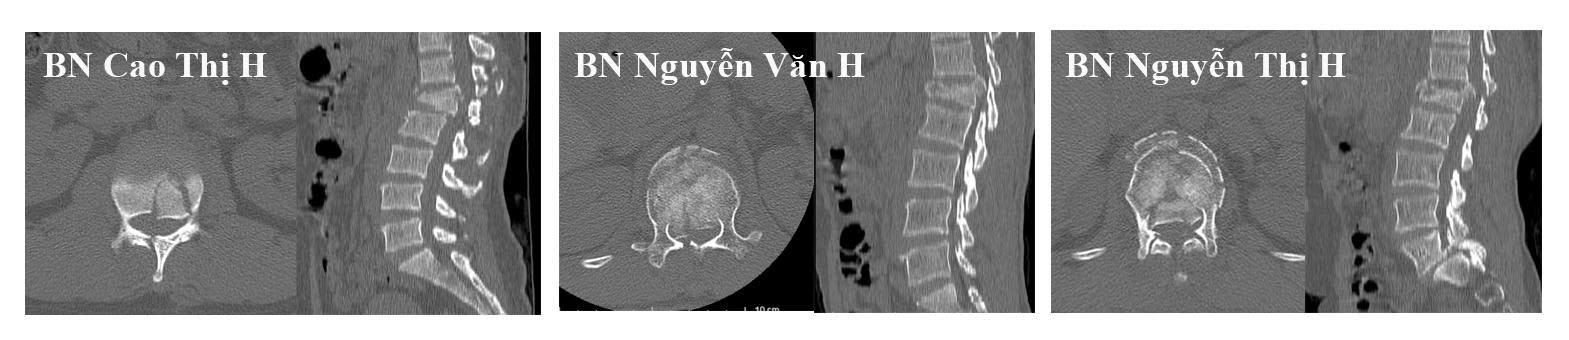

Các bệnh nhân nhập viện trong tình trạng đa chấn thương nặng sau tai nạn ngã từ độ cao khoảng 5m. Qua thăm khám lâm sàng, chẩn đoán hình ảnh và đánh giá đa chuyên khoa, cả 05 bệnh nhân đều được xác định có chấn thương cột sống, vỡ khung chậu, vỡ xương gót với mức độ khác nhau.

Hình ảnh phim chụp cắt lớp vi tính của các bệnh nhân trước mổ

Đáng chú ý có 03 bệnh nhân tổn thương nghiêm trọng, có chèn ép tủy sống, mất vận động, rối loạn cảm giác và cơ tròn đã được chỉ định phẫu thuật cấp cứu, tiến hành cố định cột sống và giải ép tủy. Sự chuyên nghiệp của kíp mổ và kíp hồi sức được phụ trách bởi BS CK2 Ngô Văn Thành (khoa phẫu thuật thần kinh cột sống), BS CK2 Lê Văn Dũng (khoa gây mê hồi sức), BS CK2 Lương Mạnh Hùng (khoa hồi sức ngoại) các ca mổ được triển khai khẩn trương nhằm giải quyết nhanh chóng tổn thương thần kinh và mất vững cột sống.